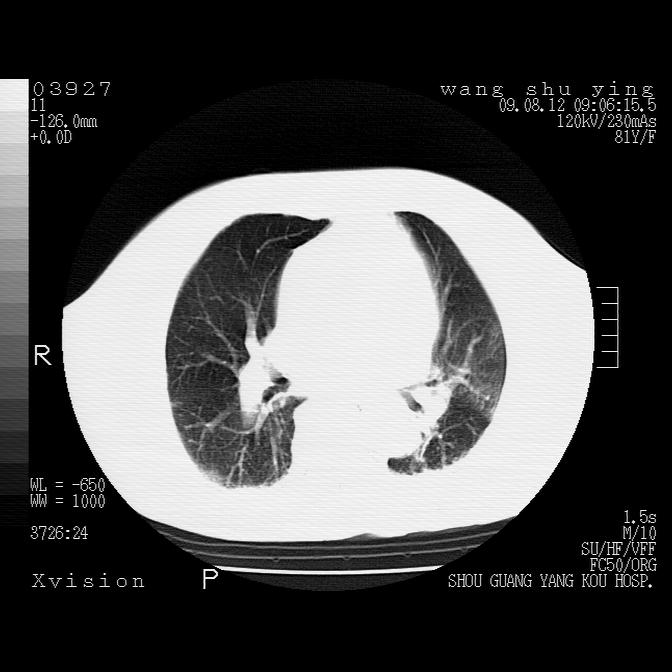

以下是引用帅河马在2009-8-12 12:59:00的发言:[br]两肺感染性病变伴双侧胸膜肥厚。[br]左侧甲状腺腺瘤不除外。[br]腹水+心包积液。[br][br][本贴已被 帅河马 于 2009-8-12 13:14:32 修改过]

以下是引用sdzyy在2009-8-12 18:17:00的发言:[br]两肺感染性病变伴双侧胸膜肥厚。[br]左侧甲状腺腺瘤不除外。[br]腹水+心包积液。[br]支持

以下是引用随光逐影在2009-8-12 19:42:00的发言:[br]1)两肺感染性病变伴双侧胸膜肥厚。2)不排除左侧甲状腺腺瘤。3)肝脏占位性病变;建议行进一步检查。